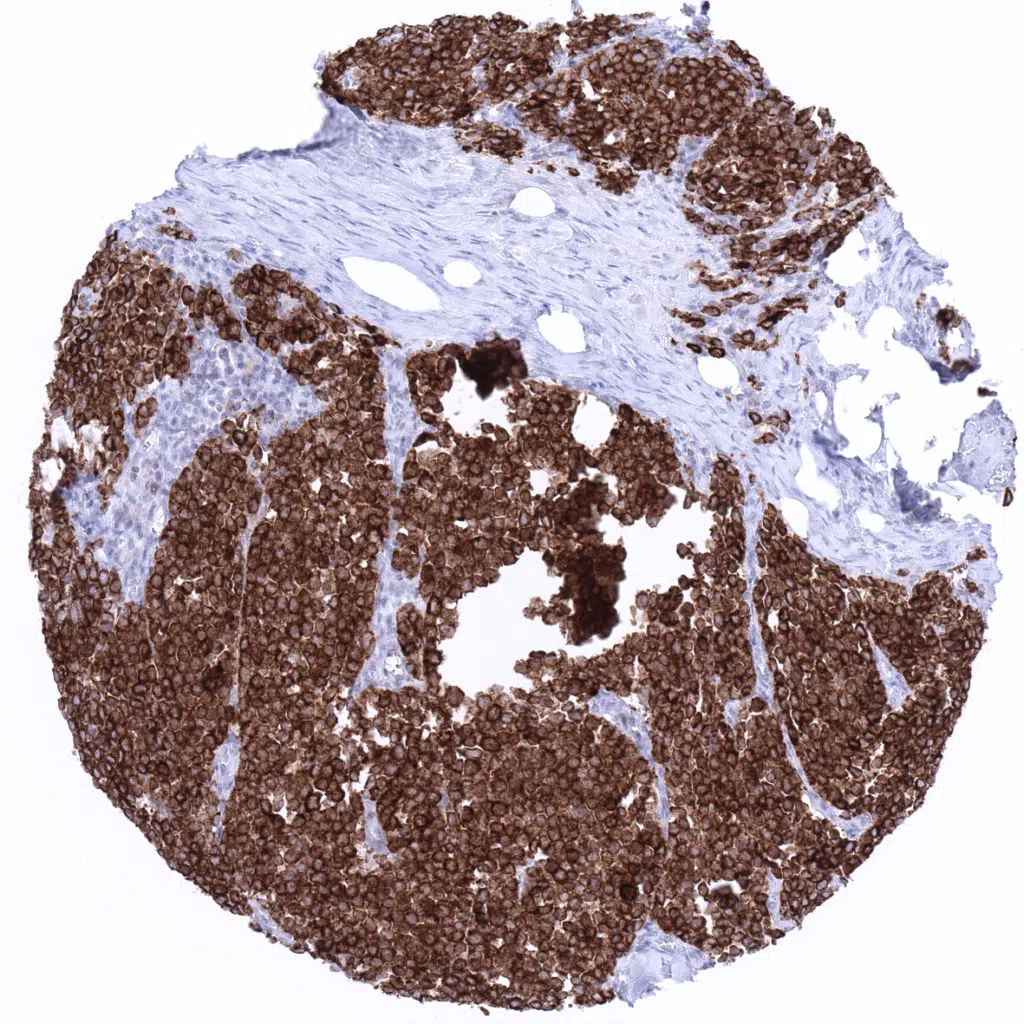

Adrenal gland - Pheochromocytoma with strong diffuse chromogranin A immunostaining.

Adrenal gland - All tumor cells show a strong chromogranin A immunostaining in a pheochromocytoma.